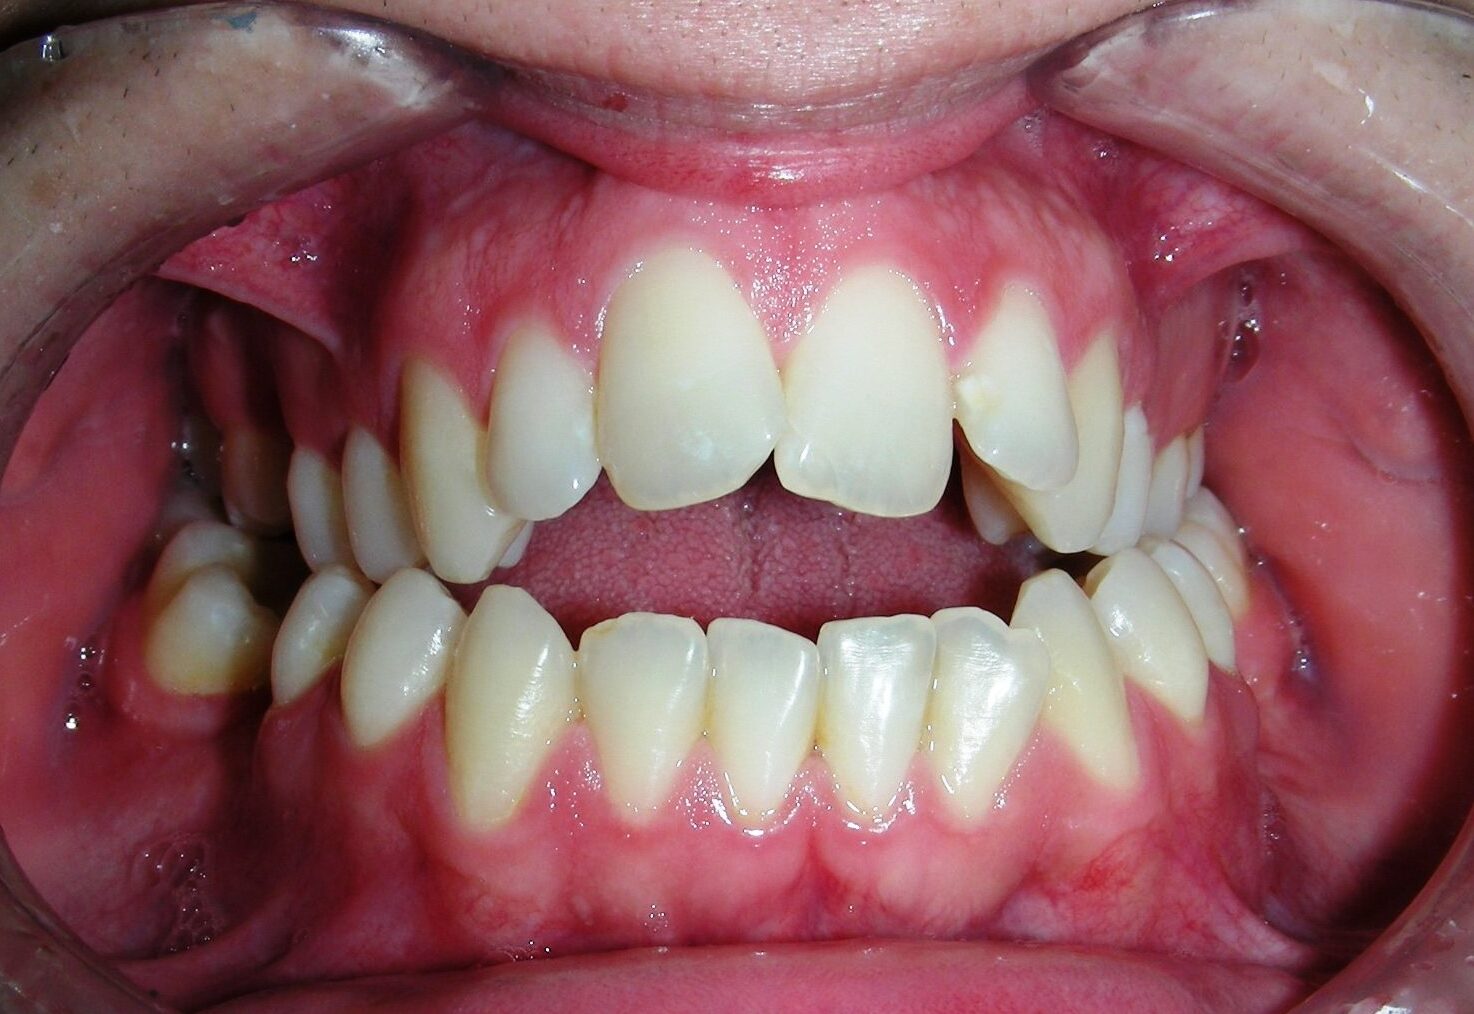

After two years of treatment using appropriate biomechanics, the overbite was successfully corrected from -8 mm to +1 mm, achieving complete closure of the anterior open bite without exacerbating the patient’s lower facial third vertical proportions. At this stage, occlusal contacts were verified using articulating paper, and functional movements of the canines and incisors were evaluated to ensure proper anterior guidance and disclusion patterns. The patient was then referred to speech therapy (myofunctional evaluation) as part of the pre-debond assessment protocol.

Finishing and Retention

At the completion of treatment (28 months) , the patient exhibited significant skeletal and dental improvements consistent with the initial treatment objectives. A reduction of 3 degrees in lower anterior facial height and a 4-degree increase in the facial axis angle were observed on post-treatment cephalometric analysis, indicating a favorable counterclockwise, anterior mandibular rotation. This skeletal change, in conjunction with the mesialization of posterior segments and space closure mechanics, led to the successful resolution of the anterior open bite. During the retention phase, a modified Hawley appliance was used in the maxillary arch, while the mandibular arch was stabilized with a fixed retainer made of twist-flex (supercable) wire #33 to #43 , which had been heat-treated to eliminate its elasticity. This retention strategy was complemented with myofunctional therapy, aimed at ensuring long-term neuromuscular stability.

The use of cephalometric measurements as quantitative indicators of skeletal and dental movement validated the biomechanical plan established from the outset of treatment. Although the patient maintains a dolichofacial biotype, the desired functional outcome—including anterior occlusal contact, vertical control, and stable mandibular positioning—was effectively achieved.